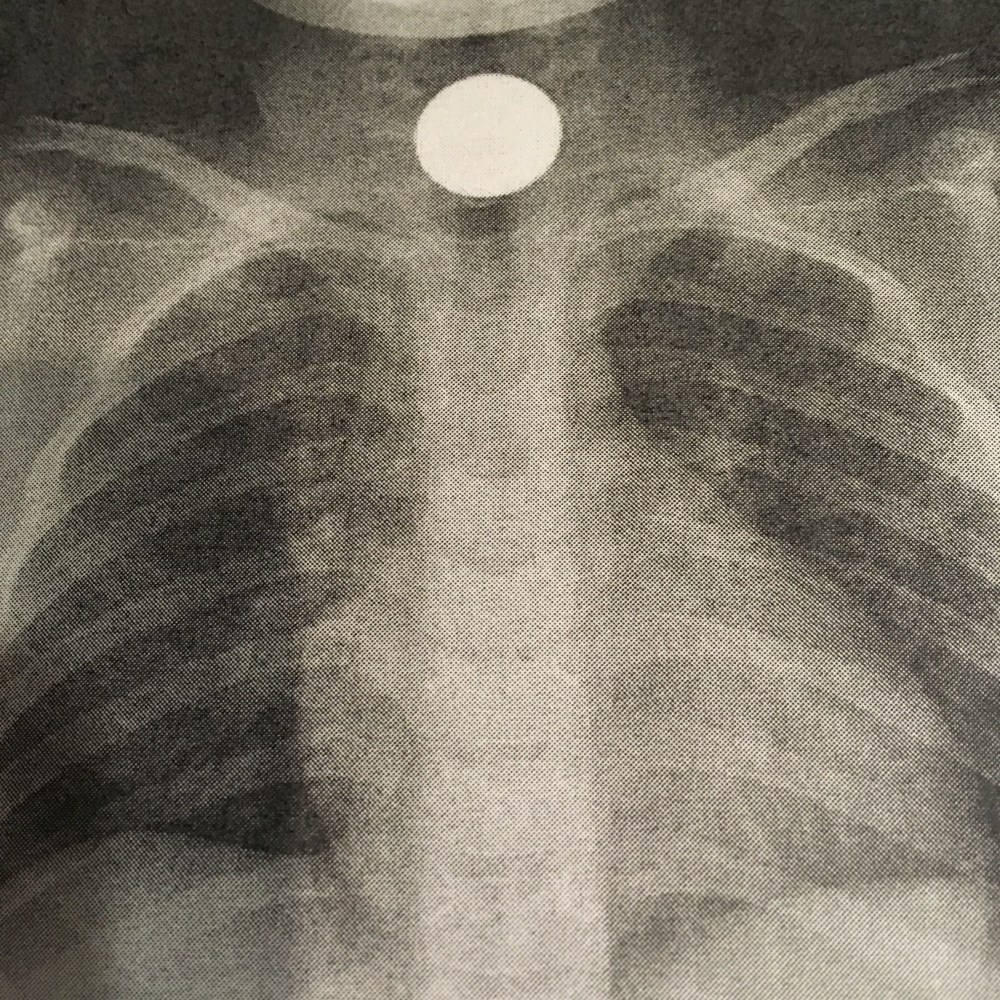

[Röntgenärztin:] „So, jetzt liegst Du hier ganz still. Und die Mama und ich gehen ganz kurz raus. [Draußen] Sehen Sie?“

[folienstern:] „Oh…“

[Röntgenärztin:] „Dann können Sie jetzt wieder in die Kinderambulanz, die entscheiden dann, was passiert.“